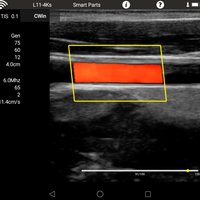

Linearsonde (L11-4Ks) 7,5 MHz 6-11 MHz L40 Gefäße, Small Parts, Anästhesie, Orthopädie

• Color: B, M, 2B, 4B, THI, Color, Power, PW